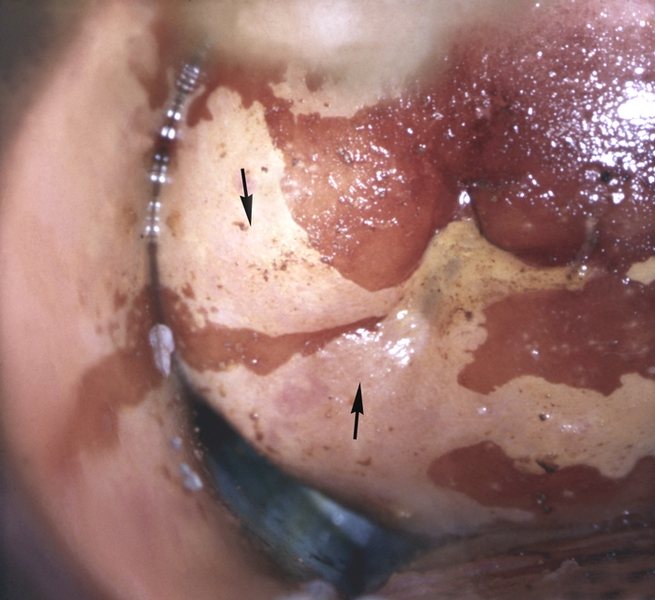

Подготовка к операции прижигания обязательно включает процедуру кольпоскопии – обследования женщины на аппарате особой конструкции с возможностью осмотра пораженного участка под увеличением в дополнительном или специальном освещении. Во время этой процедуры:

- шейка матки обрабатывается уксусной кислотой и люголем;

- проводится осмотр окрашенных участков эрозии;

- при необходимости – берется биопсия.